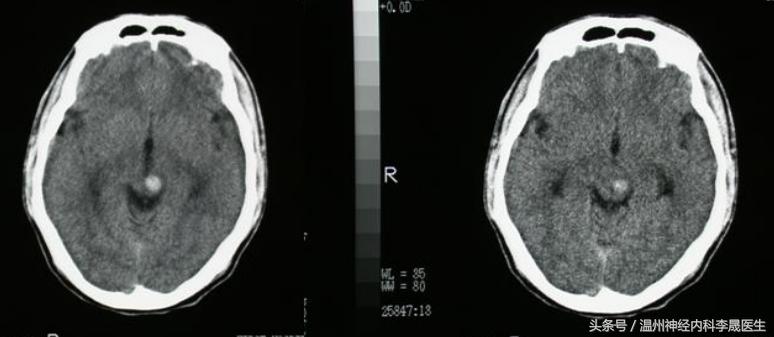

3)丘脑出血

丘脑膝状体动脉或丘脑穿通动脉破裂所致。约占10%,出血量较大时亦表现为内囊性“三偏”;

与壳核出血不同之处:

①感觉障碍较重,深感觉障碍突出;

②特征性眼征:双眼下视、凝视鼻尖、上视困难;

③意识障碍重:波及下丘脑或破入第三脑室出现中线症状(昏迷、瞳孔小、去皮层强直等)

④其他:丘脑性失语 (语言低沉、缓慢或无自发语言、听觉理解能力障碍等,但预后佳); 可有情感淡漠、视听幻觉、情绪低落、欣快以及定向、计算、记忆障碍等。

丘脑出血